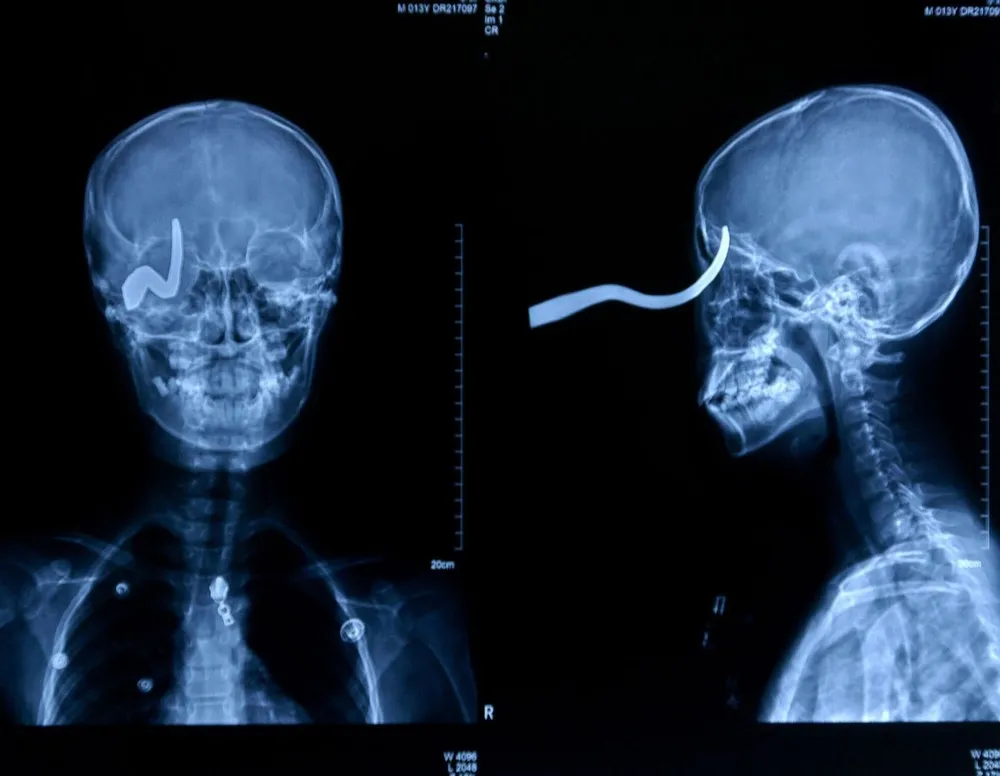

2mm from death: A 13-year-old slipped on an icy school floor in China after a faulty heater had leaked overnight. Xiao Lin fell forward onto a hook which embedded in his eye. A school handyman sawed the hook off the wall to free the lad, leaving 5cm sticking out of his head. Surgeon Yan Shijun commented: “The hook pierced his skull but was turned to the side by the impact. Any movement would have sent it into his brain and he could have died on the spot”. He added: “He has lost his right eye but he's very lucky to be alive at all”. (Photo by Rex Features)